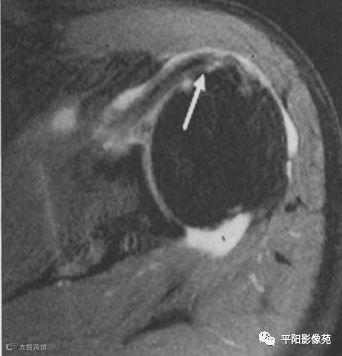

肌腱全层撕裂,示例

1、冈上肌肌腱全层撕裂,肌腱断端回缩